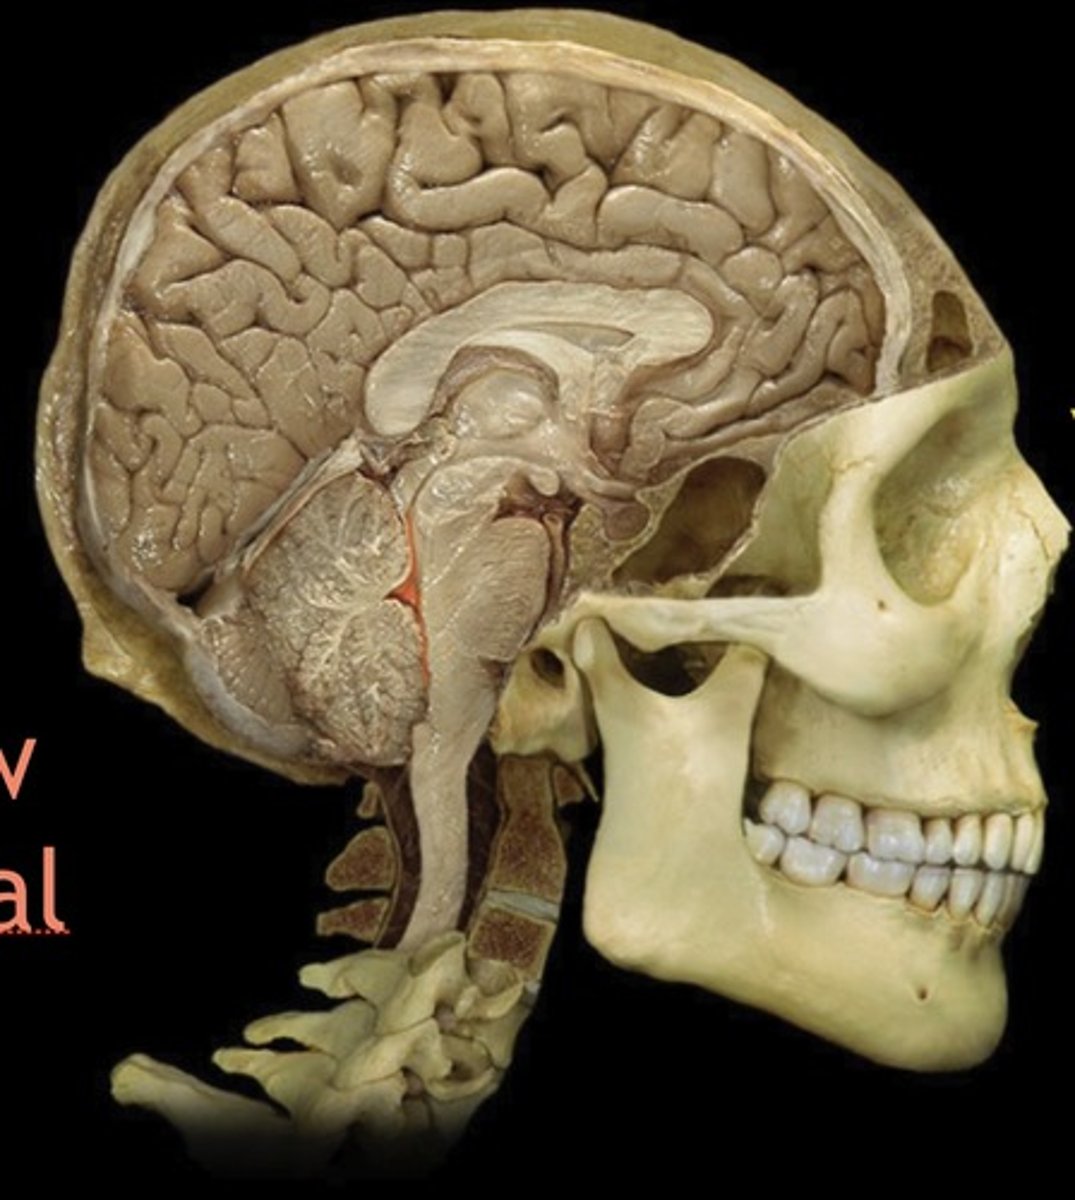

Midbrain

Name this structure

Pons

Name this structure

Fourth Ventricle

Name this structure